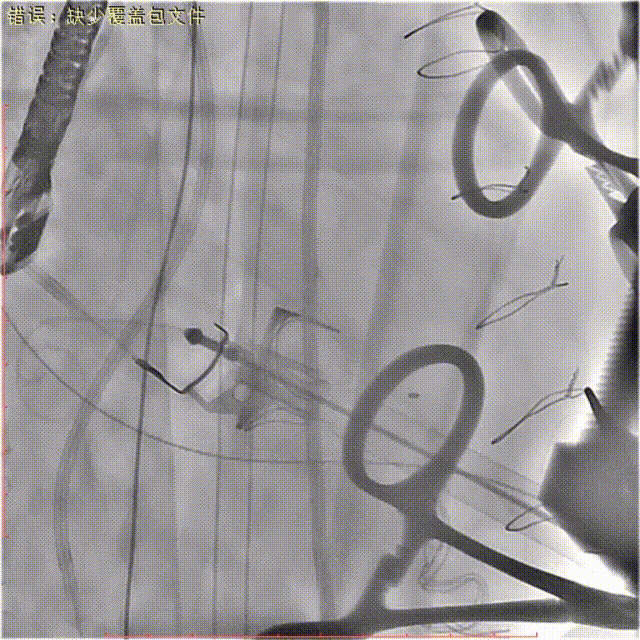

左室造影显示:二尖瓣瓣中瓣位置合适,开合良好,无瓣周漏和反流。

术后左心室造影

食道超声示:人工二尖瓣功能良好,无反流,封堵后瓣周反流基本消失。

术中及术后食道超声示:

术后食道超声

﹥TA-MVR ViV+PVL封堵术后:二尖瓣位生物瓣血流速度加快,原瓣周漏消失;

二尖瓣间隔侧探及封堵器1枚,位置固定,原生物瓣与室间隔间裂隙消失。

多普勒检查:二尖瓣位生物瓣舒张期峰值流速加快,平均跨瓣压差9mmHg,峰值跨瓣压差27mmHg,原瓣周漏消失。